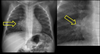

Q

Que es y como sabes

A

RX de enfisema x q hay hiperlucidez pulmonar

Se señala el corazón en GOTA